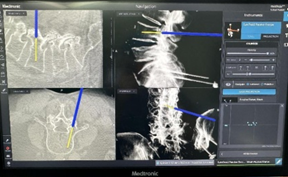

「O」型臂导航系统由「O」型臂术中影像和 Stealth Station S8 手术导航系统组成,可术中为手术医生提供 3D 立体影像,提供术前的病变定位和术中的实时引导,能让医生手术视角更广、判读脊柱状况更精确,提供精准的置钉路径,避开周围重要的血管神经,大大提高了手术安全性,缩短了手术时间,加快了患者康复。同时解决了以往术中 C 臂反复透视辐射剂量高、手术操作技术要求高、二维影像观察局限性等临床难题。